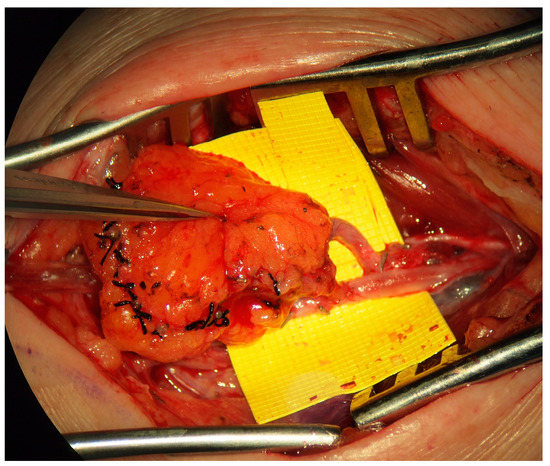

7.3. Physiologic Surgery/Microsurgery

Two forms of physiologic management are the lymphaticovenous bypass or anastomosis (LVB/LVA, Figure 4) and the vascularized lymph node transfer (VLNT) (Figure 5). Some authors have suggested that lymphatic vessel hypoplasia is not amenable to these physiologic procedures [14,15]. The use of microsurgical techniques for the management of primary lymphedema, particularly in a pediatric population, is in its infancy, and significantly more work is required to fully understand the indications, patient selection and anticipated outcomes of these procedures; the available evidence is limited to observational non-randomized studies. Meta-analysis of the available literature is precluded by the considerable variability in outcomes and inconsistency in the reporting of the degree of postoperative improvement [4]. Due to these limitations, it has been suggested that lymphatic reconstruction is not indicated for the management of primary lymphedema [2]. Early studies, however, conclude that microsurgical lymphatic reconstruction with LVB and VLNT is safe, reliable, and effective in decreasing limb volume, reducing rates of cellulitis, and improving quality of life [8,46].

7.4. VLNT

Vascularized lymph node transfers are commonly cited in the primary lymphedema literature as a treatment option for aplastic or severely hypoplastic lymphatic disease or in the presence of severe lymphosclerosis; however, these conclusions are based on very few studies. It has been suggested that lymph node transplantation may induce lymphangiogenesis [39]. A retrospective review of fifteen patients who underwent VLNT for primary lymphedema found patients had an average of 3.7 cm of limb circumference reduction as well as a statistically significant (i) decrease in the number of episodes of cellulitis and (ii) improvement in their quality of life [46]. Similarly, Ciudad et al. reported on eleven patients treated with VLNT who had an average circumference reduction of 19%; of note, this was significantly less improvement than patients with secondary lymphedema who had a 25% circumference reduction [49]. Others have reported that following VLNT, complete normalization of limb volume is achievable in 20% of patients [6]. Patients with primary lymphedema who undergo VLNT may be at an increased risk of developing heparin-induced thrombocytopenia and thrombosis (HITT), which increases the risk of flap complications [50]. Case series have suggested that combining VLNT with lipectomy may improve limb circumference and patient satisfaction [30].

As with secondary lymphedema, possible donor sites for VLNT include submental, groin, axilla, supraclavicular, omental and jejunal mesentery, and the choice is based on minimizing the risk of iatrogenic injury [51]. Choosing a safe donor site, however, is a particular challenge in primary lymphedema, given the risk of sub-clinical lymphatic dysfunction at the donor site, which may increase the risk of postoperative iatrogenic donor-site lymphedema [14,15]. The most common donor sites reported for primary lymphedema in the literature to date are submental (83%) [4]. The recipient site depends on the extent of lymphedematous disease; the VLNT should be placed at the level of the knee for isolated distal disease, whereas placement in the inguinal region is indicated for whole-lower limb involvement. Placement of the VLNT further away from the site of maximal swelling requires some lymphatic channel function. The severe lymphedematous disease may require more than one flap, one placed proximally and one more distally [39]. Complete reconstruction of a VLNT with efferent lymphaticolymphatic anastomosis is reported to successfully treat primary lymphedema [52]. A summary of reported VLNTs in primary lymphedema is summarized in Table 1.

Figure 5. Vascularized lymph node transfer. VLNT harvested from the jejunal mesentery based on branches from the superior mesenteric artery used as a physiologic treatment for aplastic primary lymphedema.